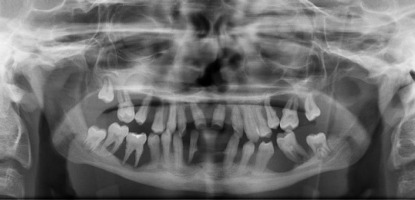

When he was 5 years of age the intraoral examination revealed incomplete primary dentition with five missing teeth, marginal gingivitis, interdental papilla hypertrophy, carious lesions in seven primary teeth, and one permanent tooth of various degrees of advancement for conservative treatment (Fig. 1). The patient was qualified for simultaneous dental treatment under general anesthesia. A panoramic radiograph picture was taken showing the advanced destruction of the alveolar bone in the maxilla and the alveolar part of the mandible. Three primary teeth were completely devoid of bone base. The roots of the lower incisors were only half of their normal length (Fig. 2). Under antibiotic protection (amoxicillin with clavulanic acid at a dose of 30 mg/kg), professional removal of dental plaque and conservative treatment of teeth extraction of four primary teeth with complicated caries and periodontitis were performed. The patient was provided with permanent dental care.

When the patient was 10, the exposure of two-thirds of palatal roots and third-degree loosening of teeth were observed (Fig. 3). A panoramic radiograph picture was taken (Fig. 4), which revealed complete absence of the bone base in all permanent first molars. Teeth 16 and 26 were qualified for extraction, which was performed in an outpatient setting under local anesthesia and antibiotic treatment (clindamycin, 10 mg/kg/dose). The obtained material from granulomatous lesions was submitted for histopathological examination, the results of which indicated non-specific inflammatory granulation tissue.